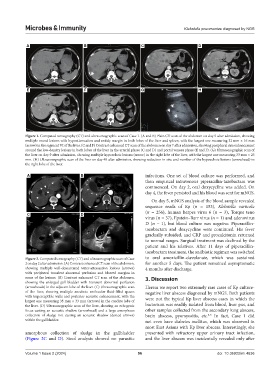

Figure 1. Computed tomography (CT) and ultrasonographic scan of Case 1. (A and B) Plain CT scan of the abdomen on day 5 after admission, showing

multiple round lesions with hypoattenuation and untidy margin in both lobes of the liver and spleen, with the largest one measuring 32 mm × 16 mm

(arrow) in the segment VI of the liver. (C and F) Contrast enhanced CT scan of the abdomen on day 7 after admission, showing peripheral rim enhancement

around the low-density lesions in both lobes of the liver in the arterial phase (C and D) and portal venous phase (E and F). (G) Ultrasonographic scan of

the liver on day 9 after admission, showing multiple hypoechoic lesions (arrow) in the right lobe of the liver, with the largest one measuring 33 mm × 25

mm. (H) Ultrasonographic scan of the liver on day 48 after admission, showing reduction in size and number of the hypoechoic lesions (arrowhead) in

the right lobe of the liver.